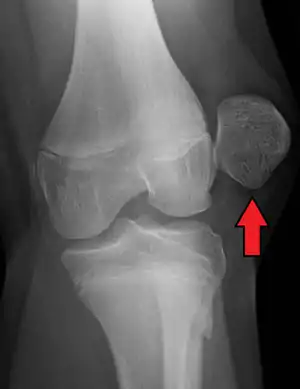

A patellar dislocation is a knee injury in which the patella (kneecap) slips out of its normal position.[5] Often the knee is partly bent, painful and swollen.[1][2] The patella is also often felt and seen out of place.[1] Complications may include a patella fracture or arthritis.[3]

| X-ray showing a patellar dislocation, with the patella out to the side. | |

A patellar dislocation typically occurs when the knee is straight and the lower leg is bent outwards when twisting.[1][2] Occasionally, it occurs when the knee is bent and the patella is struck directly.[1] Commonly associated sports include soccer, gymnastics, and ice hockey.[2] Dislocations nearly always occur away from the midline.[2] Diagnosis is typically based on symptoms and supported by X-rays.[2]

Displacement of the patella laterally out of its groove strains the medial stabilizing connective tissues, particularly the medial patellofemoral ligament (supporting 50–80% of the knee mechanisms in lateral patellar glide), which is torn usually at its femoral attachment.[3] Traumatic patellar dislocation may cause bleeding into the joint space, ligament and muscle attachment tearing, and fracture of the medial wing of the patella.[3] Fracture of the weight-bearing portion of the lateral femoral condyle occurs in 25% of traumatic patellar dislocations.[3] Surgical repair of the patellar stabilizing structures – the medial patellofemoral ligament and vastus medialis muscle – may be needed for athletes.[3]